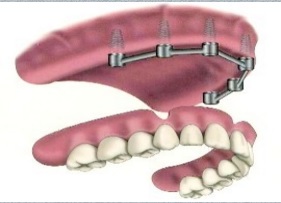

اوردنچر بر پایه ایمپلنت دندان

اوردنچر چیست؟ در روش اوردنچر بر پایه ایمپلنت دندان از چند ایمپلنت در فک بیمار استفاده می شود که این امر باعث گیر و ثبات دست دندان مصنوعی بیمار می شود. زمانی که یک دنچر کامل به یک اوردنچر متکی بر ایمپلنت دندان تبدیل می گردد عملکرد جویدن بهبود می یابـد.

در روش اوردنچر متکی بر ایمپلنت در مقایسه با روش پروتز ثابت متکی بر ایمپلنت دندان نیاز به ایمپلنت کمتری است که این امر باعث ارزان تر شدن این روش در مقایسه با پروتز ثابت متکی بر ایمپلنت شده است.

در استفاده از اوردنچر دو روش ball و bar مطرح است که در روش bar باعث کاهش انتقال استرس به استخوان اطراف ایمپلنت می شود و در Ball افزایش Stability اوردنچر را داریم.